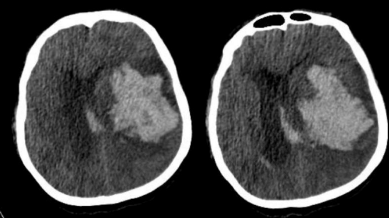

Paciente do sexo masculino, 72 anos, deu entrada no departamento de emergência com história de cefaleia súbita, evoluindo com vômitos e rebaixamento do nível de consciência. Antecedente de hipertensão arterial sistêmica e tabagismo, porém familiares não sabem referir nome das medicações em uso. Necessitou de intubação orotraqueal para proteção de vias aéreas. No momento, em ventilação mecânica modo assistido-controlado. Pressão arterial: 160x100mmHg. Frequência cardíaca de 78 batimentos por minuto. Anisocoria (midríase à esquerda). Exames laboratoriais evidenciaram: hemoglobina 13g/dL, leucócitos 13.000/mm3, plaquetas 220.000/mm3, ureia 60mg/dL, creatinina 1,6mg/dL, tempo de protrombina com INR (international normalized ratio) de 4,20, tempo de tromboplastina parcial ativado com relação P/N (paciente/normal) de 1. Tomografia de crânio sem contraste evidenciou o resultado a seguir. |